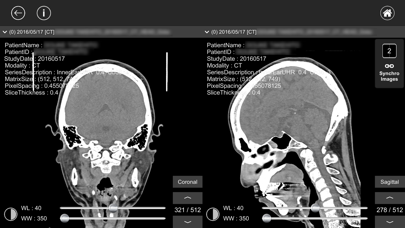

- 2画面機能で画像間の比較ができます。

- シンクロ機能で2画面を同時に操作できます。

- CTやMR画像などは横断面(Axial)から再構成した冠状面(Coronal)、矢状面(Sagittal)画像を閲覧することができます。(3次元再構成)

- 2画面機能で画像間の比較ができます。

- シンクロ機能で2画面を同時に操作できます。